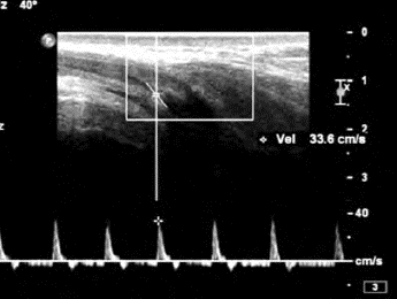

2.静脉性阳萎 注药后,阴茎深动脉峰值速度正常(Vmax> 30~35cm/s)(图31-10),连续测试5~30min,频谱始终呈单峰血流图形,通常RI≤0.7,舒张期血流>5cm/s。

图31-10 静脉性阳痿频谱图

频普呈单峰,峰值速度正常